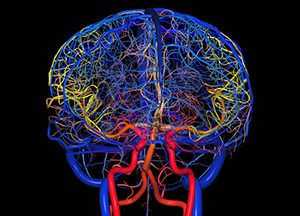

Общие сведения о базальном кровообращении, его сосудистой структуре и её функциях

Виллизиев круг является самым началом всей кровеносной сети, поднимающейся от основания головного мозга вверх как по его поверхности, так и в недрах, чтобы далее, бесконечно ветвясь, достигнуть каждой отдельной клетки в его тканях и структурах.

Замкнутая в кольцо артериальная система позволяет осуществлять свою основную функцию (бесперебойное снабжение мозга кровью) как нельзя более успешно, ибо при появлении перебоев с питанием из одного сосуда происходит автоматическое переключение на кровоснабжение из другого.

А возникнуть перебои питания могут по причинам появления в одной из артериальных ветвей:

- спазма;

- сужения просвета другой этиологии (вследствие образования холестериновых отложений, тромба, утолщения стенки от образования рубца, ввиду пережатия извне);

- аневризматической деформации просвета;

- атрофии или запустения (спадения с заращением просвета – облитерацией).

Либо это может быть последствие гипоплазии (врождённого недоразвития), сказавшегося в критический момент.

Развитие Виллизиева круга

Виллизиев круг — система церебральных артерий, расположенных в области основания головного мозга. Она компенсирует дефицит кровотока с помощью дополнительных сосудистых бассейнов. Патологическое развитие виллизиева круга может стать причиной формирования заболеваний. Рассмотрим основные методы диагностики патологий.